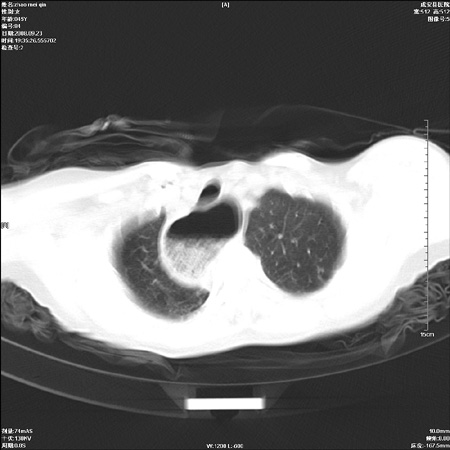

标题: CT15861:女 60 外伤后1小时 胸疼 [打印本页]

标题: CT15861:女 60 外伤后1小时 胸疼

外伤后1小时 胸疼 是外伤后引起的吗?

食道扩张明显下端逐渐变窄,倒像贲门失迟缓

非外伤性改变,典型的贲门失迟缓症

食道扩张明显下端逐渐变窄,大量食物存留,象贲门失迟缓症。